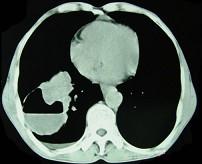

问题 男,76岁,胸痛伴咳嗽,咯血低热1个月,CT检查如图,最可能的诊断为 ( )

选项 A.右下肺脓肿 B.右下肺癌伴空洞形成 C.右下肺囊肿 D.右下肺包虫病 E.右侧包裹性积液

答案 B